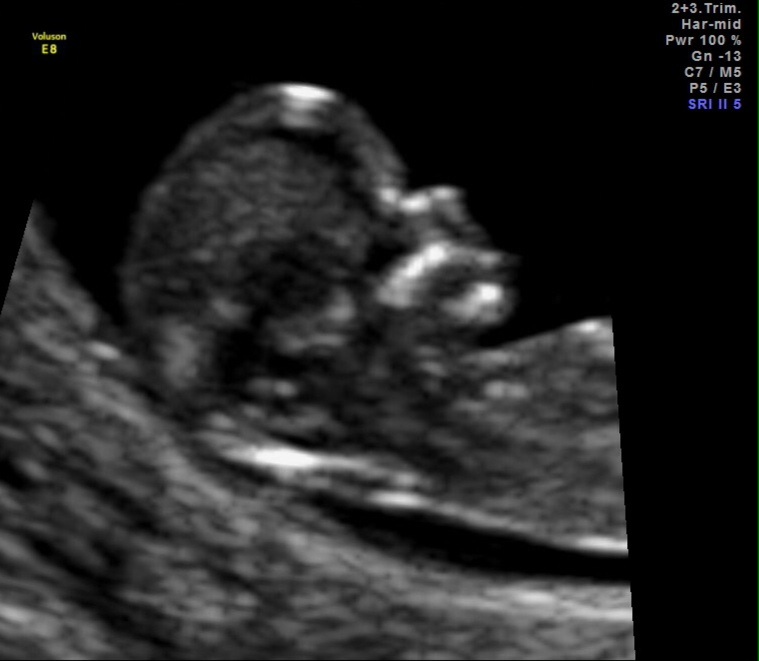

I have my anatomy scan next week so I'm just curious to see what you all think based on these two theories. So, what's your thought boy or girl? Thanks.Attachment 15671Attachment 15672

Very clear boy nub

looks boy to me too

boy

That's definitely a boy.